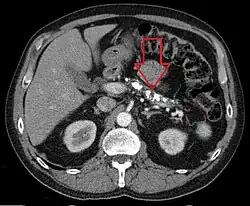

![]() Liczne zwapnienia w trzustce u chorego chorego na przewlekłe zapalenie trzustki, obraz TK | |

Obecność widocznych w badaniach obrazowych zwapnień i złogów jest charakterystyczne dla przewlekłego zapalenia trzustki (szczególnie postaci alkoholowej). Inną charakterystyczną zmianą w badaniach obrazowych jest nieregularne poszerzenie głównego przewodu trzustkowego i jego gałęzi.